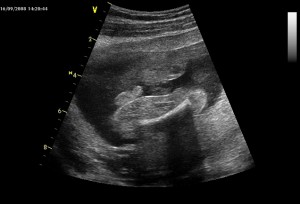

A tady podle té fotky poznali, že jsem chlapeček… to co je mírně vlevo od prostředka, to by měl být pindík a pod ním kousek nožičky, stehýnko a stehenní kost. Druhá nožička už není tolik vidět. Jestli to ještě někdo nevidí, tak jako další nápověda je, že jsem v poloze na zádech, mám hodně skrčené nožičky a vystrkuju zadeček…

Už to vidíte? Ale myslím, že bude nejlepší si počkat, až to uvidíte ve skutečnosti...